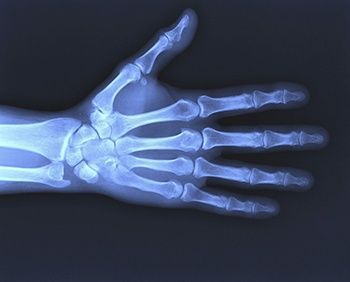

Рентген кисти

Кисть руки является дистальной частью верхней конечности, которая имеет сложное анатомическое строение. Рентген кисти представляет собой диагностическую методику, которая позволяет провести исследование её костных структур и суставов, оценить их состояние и выявить имеющиеся патологии и изменения, которые они вызвали. Своевременно проведённая диагностика позволяет исключить целый ряд серьёзных осложнений, ограничивающих подвижность кисти. Это актуально для любого пациента, поскольку руки и пальцы являются важнейшим инструментом человеческого тела, позволяющим выполнять большое количество задач.

Ежедневно кисти рук подвергаются серьёзным нагрузкам разной природы, поэтому подвержены не только заболеваниям, но и травмам. Это делает их диагностику особенно востребованной. Рентгенография отличается невысокой ценой и доступностью. Она абсолютно безболезненна и требует минимума времени, но при этом имеет высокую информационную ценность.

Рентгенологическое исследование кисти руки позволяет получить данные о воспалительных процессах лимфоузлов, патологических процессах мышечных тканей и сухожилий. Благодаря ему хорошо просматривается вся структура кистей, их отделы, костные ткани, суставы, связки, а также любые их повреждения, начиная с трещин и заканчивая переломами.